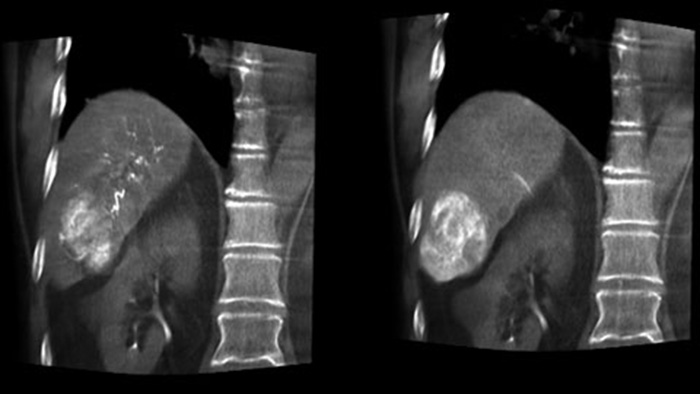

Una adquisición 3D posterior a la embolización le permite visualizar la deposición dirigida de material embólico, como Liopidol o perlas radiopacas, en el tumor.5.

Dual View permite la visualización simultánea de la imagen 3D de fase arterial antes de la embolización y la imagen después de la embolización para evaluar el criterio de valoración del tratamiento.